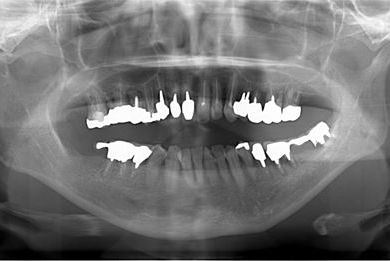

インプラントの症例写真 IMPLANT

骨再生スピードインプラント治療+セラミック治療

| 治療方針 | サイナスリフトにて上顎洞を拳上し、インプラント治療を可能にする。抜歯と同時にインプラント埋入を行い、治療期間を短縮する。 | ||||||||||||||||||||||||||||||||

| 治療内容 | インプラント9本(抜歯即日スピードインプラント、サイナスリフト)、ハイブリッドセラミッククラウン12本(ハイブリッドセラミック用土台3本) | ||||||||||||||||||||||||||||||||